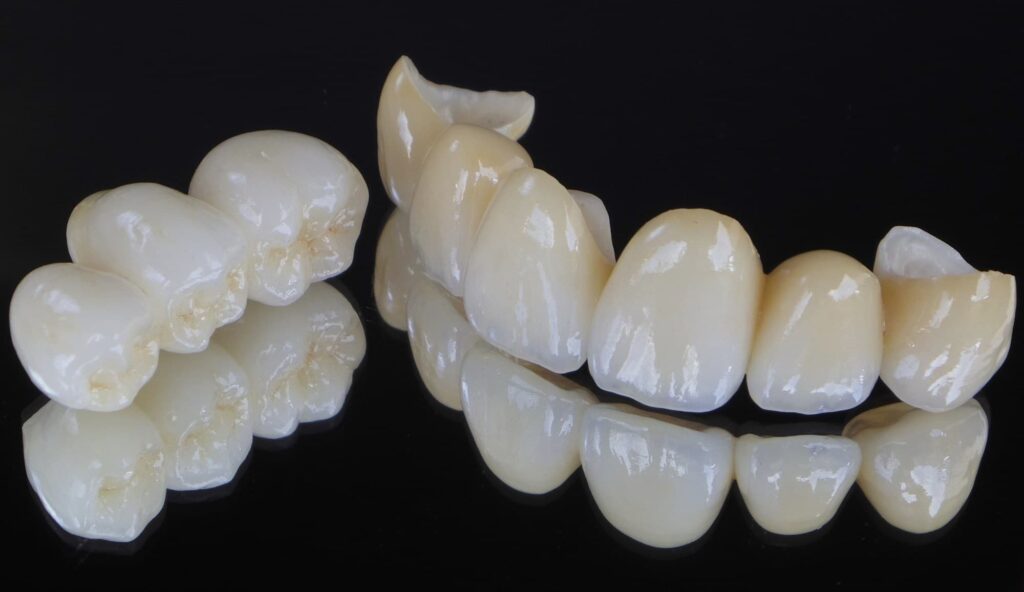

・高精度なセラミック治療: 汚れ(プラーク)が付着しにくく、歯茎との親和性が高い素材です。接着技術の進化により、自分の歯と一体化するように強固に固定できます。